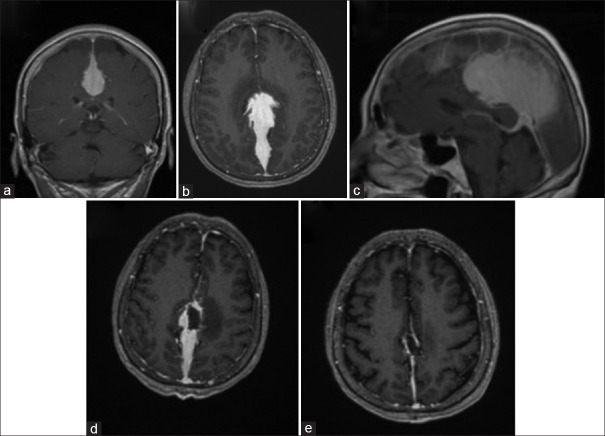

Solitary intradural plasmacytomas are extremely rare. We present a case of a patient with headache and diagnosis of meningiomatosis. Onset symptoms were abrupt neurological deterioration and paraparesis. The patient underwent surgery by craniotomy and tumor resection, with final pathological findings of solitary extramedullary plasmacytoma without evidence of multiple myeloma. Of note is the great similarity of this infrequent pathology with meningiomas and the need to differentiate it from the dural involvement of multiple myeloma. Treatment always includes tumor resection surgery and postoperative radiotherapy.